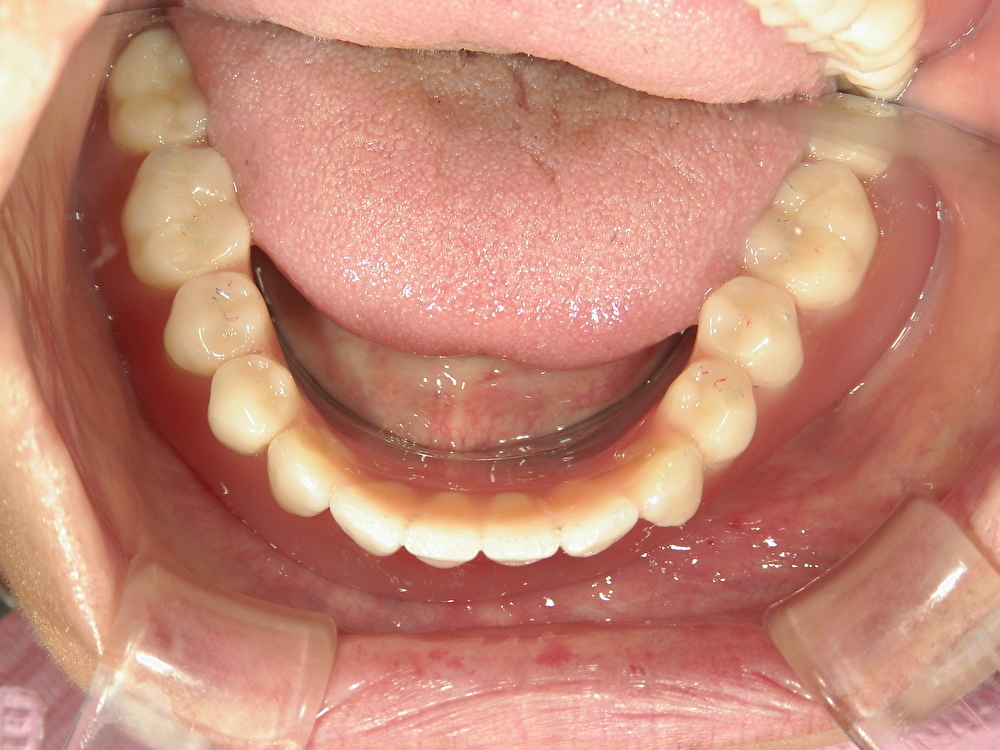

▼ 来院時の状態

現在お使いの入れ歯は、これまで何度も調整を繰り返した結果、形がいびつになっていました。また、もともとの顎の形(歯ぐきの土台)が細く、痩せている状態で一般的な入れ歯では

- ・吸着(くっつき)が得られにくい

- ・動きやすく、痛みが出やすい

- ・噛むと浮く・ズレる

といった問題が起こりやすい状況でした。